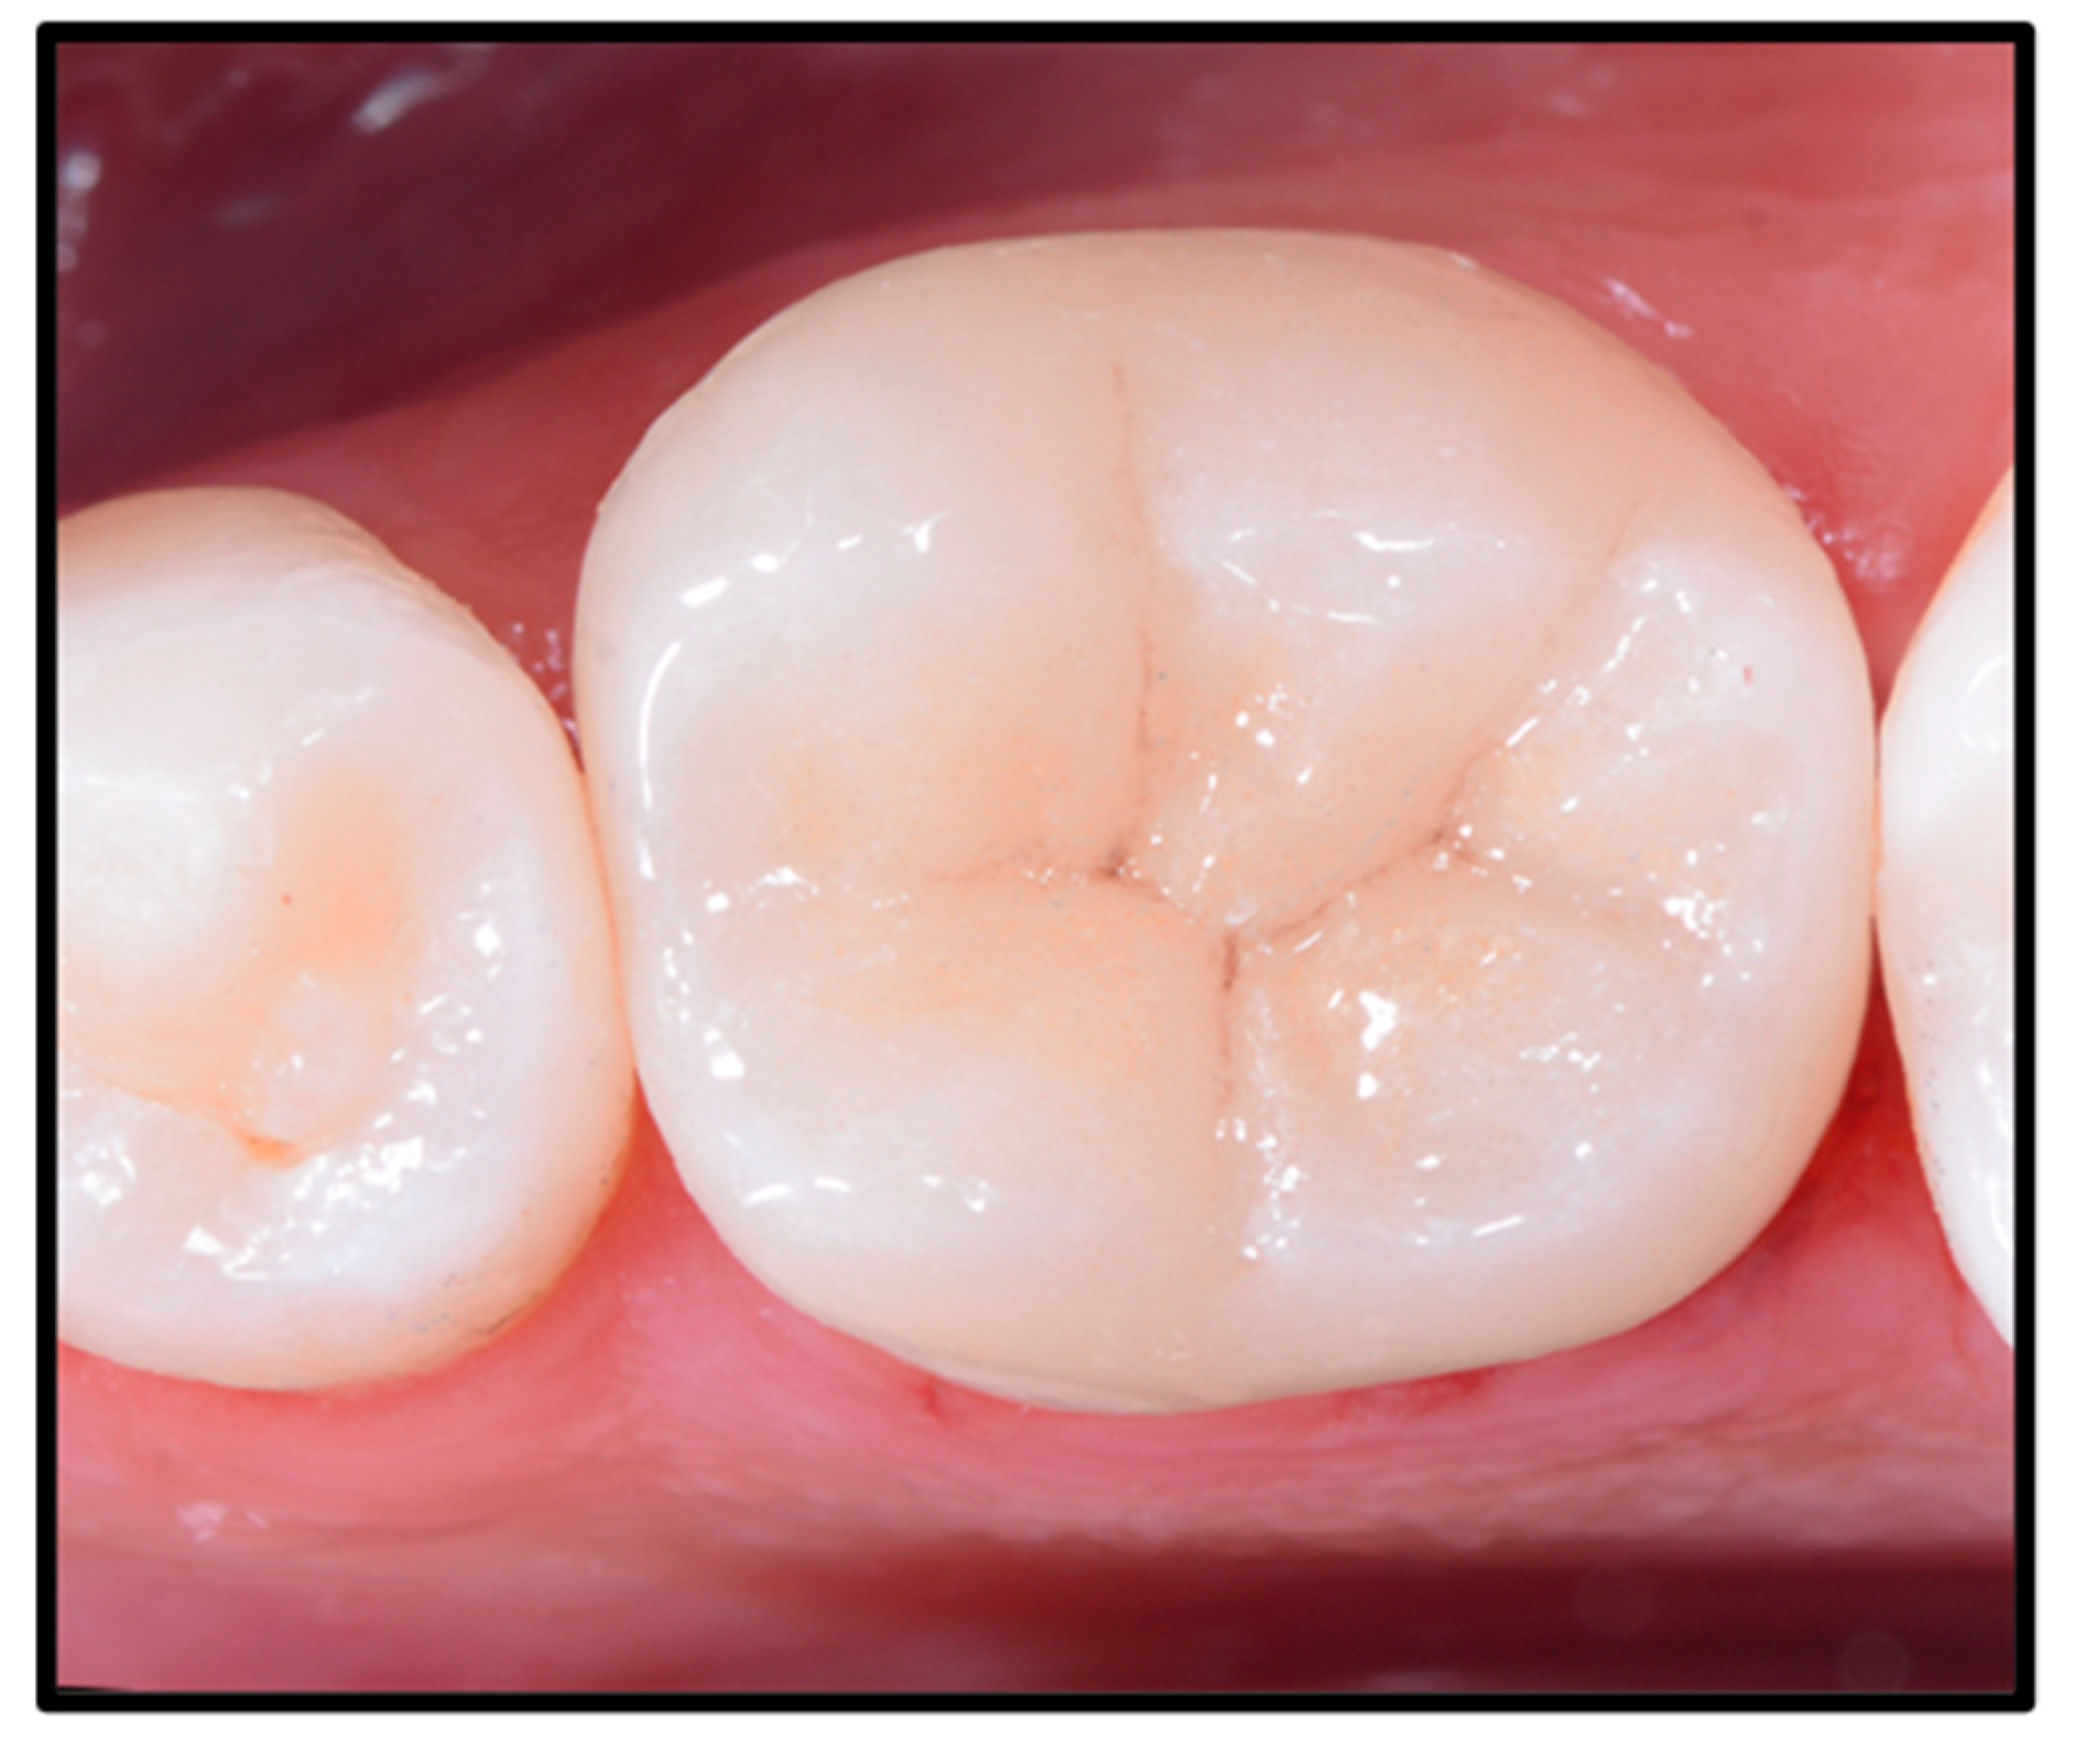

2. Case Report